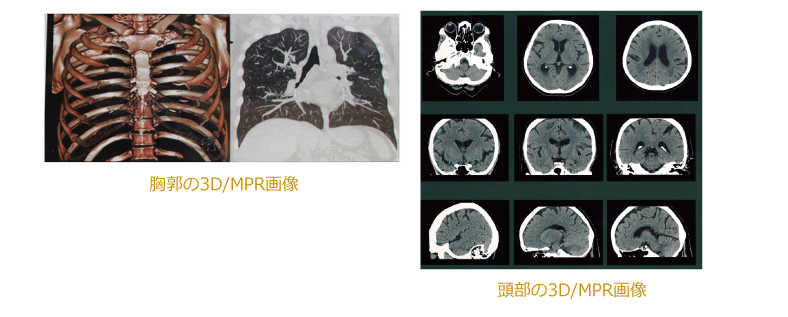

●冠状断・矢状断・3次元立体画像表示が可能で、従来のCTではで難しかった

小さな病変も画出しやすくなり早期発見が可能です。